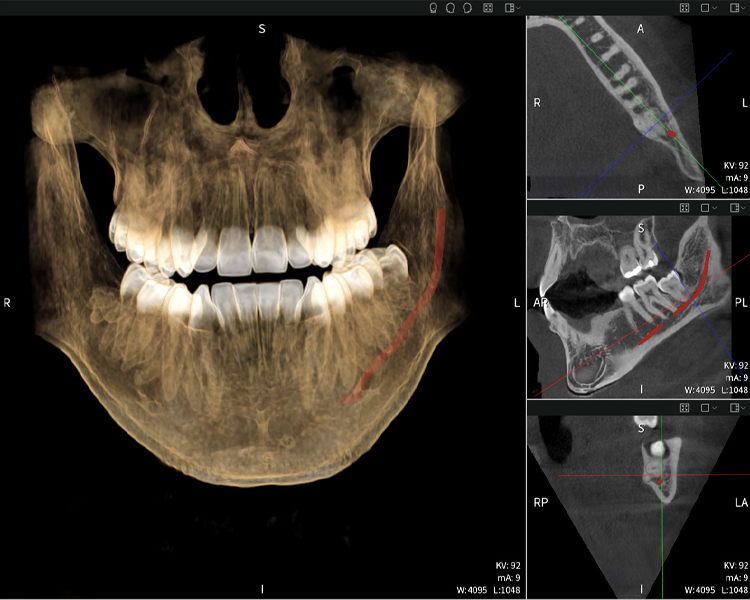

Figures b–d show various views of a 3D reconstruction of the mandible, providing a comprehensive overview of the mandibular anatomy, the position of the nerves in relation to the teeth, and allowing assessment of tooth symmetry and alignment.

Figure d shows the previously treated tooth 48, with its crown removed, and its roots left in proximity to the nerve, illustrating the high risk of nerve damage.

Figure e: The panoramic X-ray serves as an initial assessment tool, showing the general positioning of the teeth as well as any potential pathological changes. Notably, on the right side (tooth 48), the situation following a crown amputation performed by an external practitioner is visible. The two severely curved roots remain in close topographical proximity to the inferior alveolar nerve within the bone. This suggests a deliberate decision to avoid the increased risk of nerve injury during a complete extraction, and represents a clinically relevant finding. In summary, CBCT scans with Seethrough Max, provide crucial information about the complex anatomy and the critical relationship between the wisdom teeth and the inferior alveolar nerve. This detailed preoperative diagnostic imaging is essential for safe and successful surgical procedures in the mandibular region.